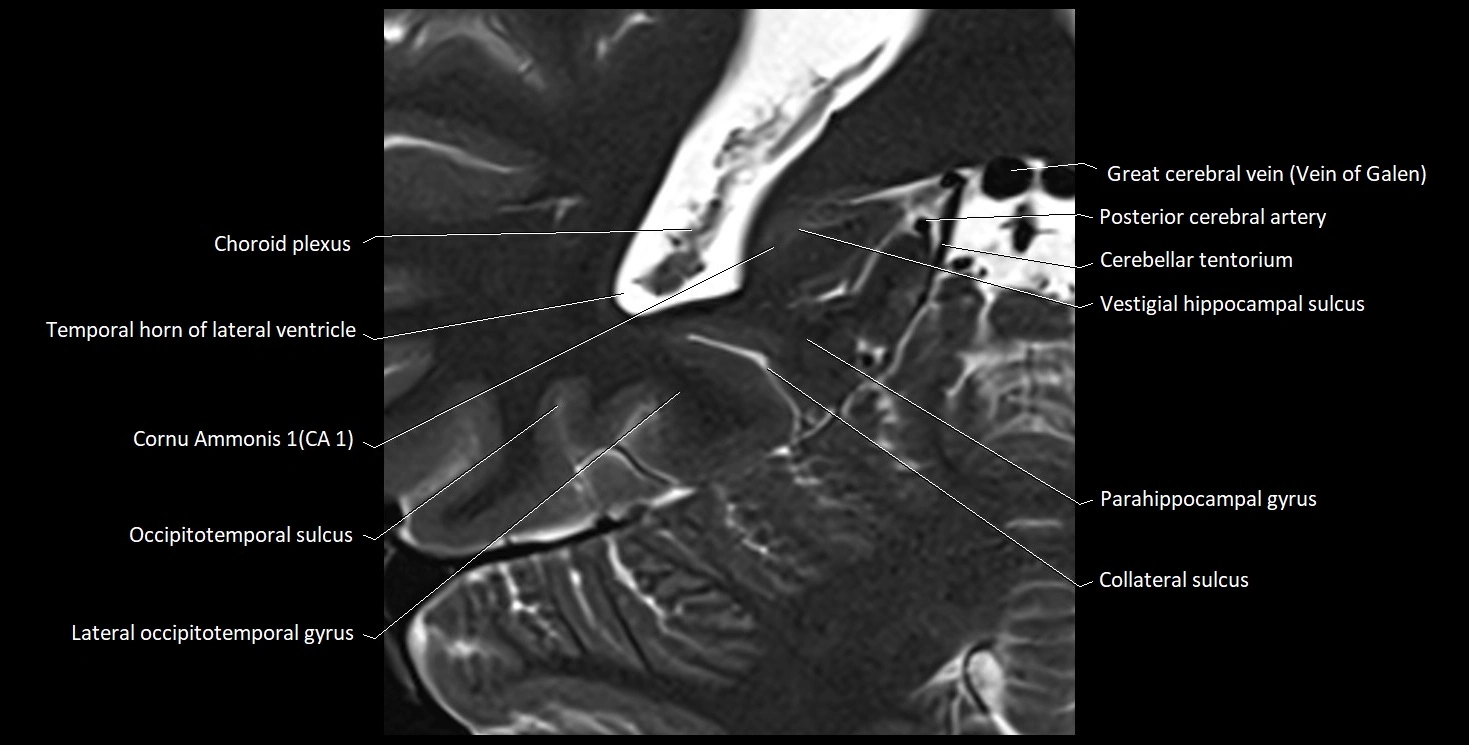

MRI images

image